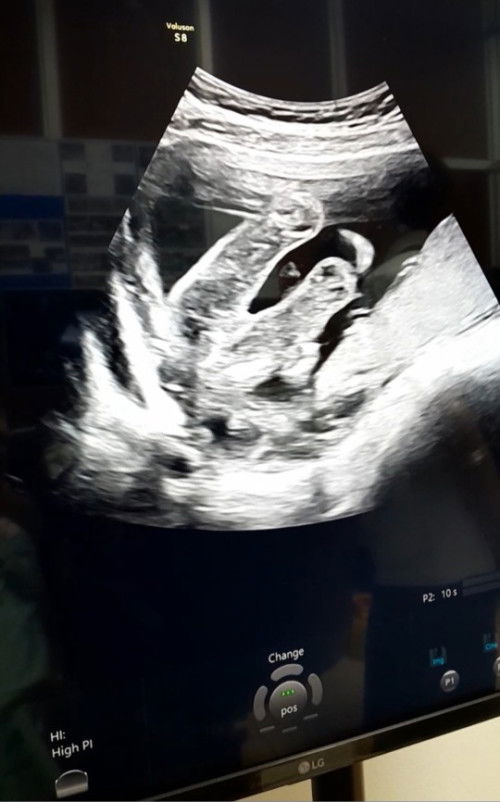

วันนี้วันที่03/07/66 ได้พาเจ้าตัวน้อยไปฝากครรภ์ที่โรงพยาบาล ตอนคุณหมอ(หมอจบใหม่)อัลตราซาวด์ผ่านหน้าท้องยังเห็นตัวน้องไม่ค่อยชัดแต่พบถุงการตั้งครรภ์อยู่ในมดลูกปกติน่าจะด้วยอายุครรภ์ยังน้อยใจนึงก็แอบกังวลนิดๆ แต่พอออกมาจากห้องอัลตราซาวด์ก็ได้นั่งรอซักพักจนพี่ผู้ช่วยพยาบาลมาเรียกให้เราไปเปลี่ยนผ้าถุงแล้วไปอัลตราซาวด์ใหม่อีกครั้ง(โดยหมอประจำเวร)โดยตรง แต่เป็นการตรวจผ่านทางช่องคลอดคราวนี้เห็นตัวน้องชัดมากได้ยินเสียงหัวใจของน้องแล้วมันเป็นวินาทีที่เหมือนโลกทั้งโลกเปลี่ยนไปเลยดีใจแบบบอกไม่ถูกเลยค่ะ ปล.ครั้งนี้ไปฝากรพ.ครั้งหน้าไปฝากพิเศษดีกว่าเสียตังแต่สบายใจอะไรที่ดีสำหรับลูกแม่ก็จะทำไม่งั้นมั่วไปหมด #6w6d #ท้องแรก #เกาะแม่ไว้แน่นๆนะลูก🤰🏻